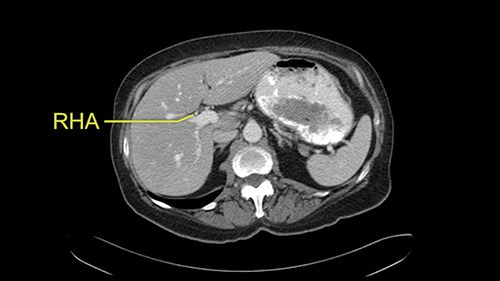

So I would then focus on the hepatic outflow because that’s the way we do the operation is by mobilizing the liver. So the vena cava looks quite normal. The right hepatic vein looks quite normal. There are no large additional outflow veins from the right lobe which would generate slowing down moments. The hepatic artery is unremarkable and is not usually an issue we can define the anatomy quite clearly at surgery.

![[RHA]](jpg/preop_sg_moment3.jpg)